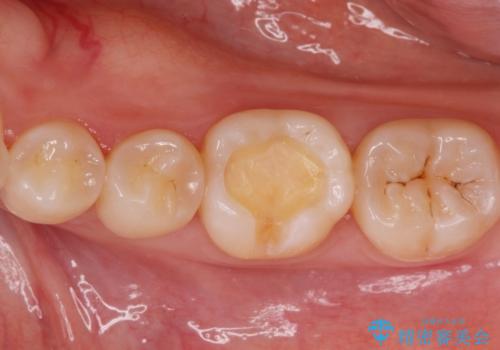

- 銀の詰め物のやりかえを希望された患者様です。

白い歯にしたいとの事だったのでセラミックインレー(e-maxインレー)にて治療しました。